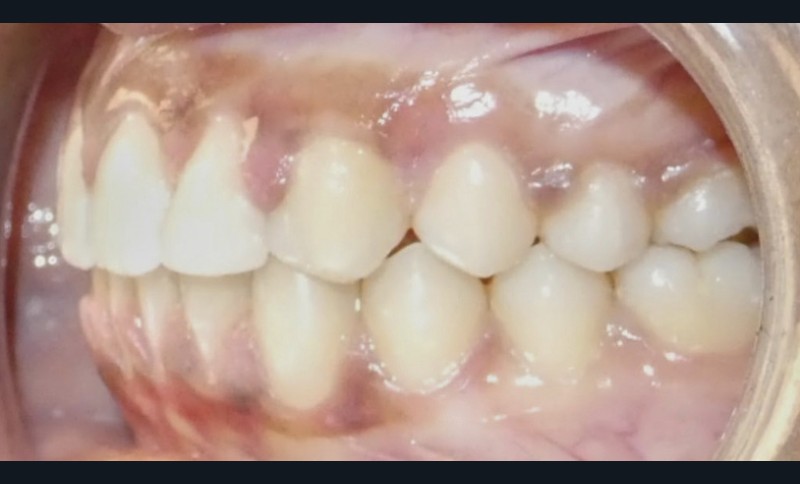

Diagnostic (fig. 1 et 2)

À l’examen extra-oral, la patiente présente un profil biprognathe associé à une Classe II squelettique modérée dans un contexte de normodivergence. L’angle naso-labial apparaît ouvert, le sillon labio-mentonnier est marqué et une prochéilie mandibulaire est observée. Le sourire se révèle disharmonieux, avec une faible visibilité des dents maxillaires.

À l’examen intra-oral, les arcades sont paraboliques, la courbe de Spee est normale. On remarque l’absence de la 23 sur l’arcade ainsi que la persistance de la 63. La patiente présente une Classe II partielle molaire et canine subdivision droite, ainsi qu’une insuffisance de recouvrement. Un léger encombrement incisif mandibulaire est présent, ainsi que des diastèmes maxillaires avec une dysmorphie dento-dentaire de 12 et 22.